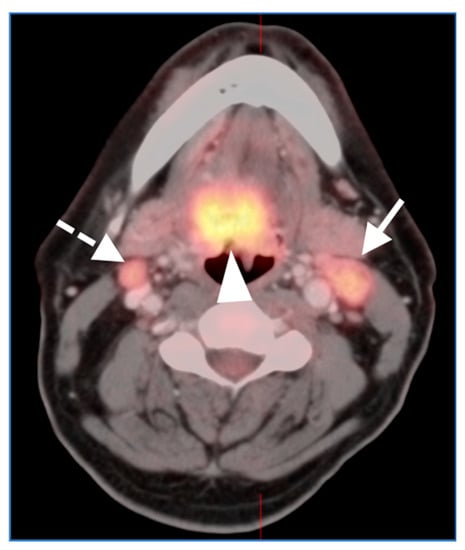

2.2. Squamous Cell Carcinoma of the Head and Neck (SCCHN)

- Oropharyngeal squamous cell carcinoma

- Laryngeal squamous cell carcinoma